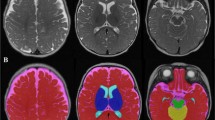

Imaging Data Acquisition and Processing

Infant MRIs were performed on a 3.0 T Siemens Skyra scanner, with a 64-channel head coil. Infants were scanned during natural sleep, with no sedation. The T1-weighted acquisition used an advanced version of the Magnetization Prepared Rapid Acquisition Gradient Echo (MPRAGE) sequence, where fast, low resolution volumetric navigators were played each repetition period and were used for prospective motion correction (Tisdall et al., 2012). The specific imaging parameters of the MPRAGE acquisition included: voxel size = 1 × 1 × 1 mm3, repetition time (TR) = 2500–2540 ms, echo time (TE) = 1.65–2.37 ms, inversion time (TI) = 1450–1470 ms, field of view (FOV) = 192 × 192 mm2 and between 144–173 slices, enough to cover the entire brain of the infant. After performing visual quality control using the Freeview software (surfer.nmr.mgh.harvard.edu), the T1-weighted volumes were manually aligned along the AC-PC plane, and underwent N4 bias correction (Tustison et al., 2010), field of view normalization (Ou et al., 2018) and multi-atlas skull stripping (Doshi et al., 2013). These steps were followed by automatic segmentation into cortical and cerebellar gray and white matter as well as subcortical gray matter regions, including amygdala and hippocampus, using a multi-atlas-to-subject registration and fusion (Doshi et al., 2016), that have been validated (Ou et al., 2011, 2014) and adapted to infant brain MRIs (Morton et al., 2020; Ou et al., 2017). Quality control of the segmentations was visually performed using the FslView software (https://fsl.fmrib.ox.ac.uk/). These segmentations enabled the extraction of GMV (total of cortical, cerebellar and deep gray matter) and WMV (total of cerebral and cerebellar white matter). In addition, the right and left hemisphere amygdala and hippocampal volumes were extracted from the deep gray volumes.

These steps were followed by automatic segmentation into cortical and subcortical regions as well as tissue types classification using a multi-atlas-to-subject registration and fusion (Doshi et al., 2016) that have been validated (Ou et al., 2011, 2014) and adapted to infant brain MRIs (Morton et al., 2020; Ou et al., 2017). Quality control of the segmentations was visually performed using the FslView software (https://fsl.fmrib.ox.ac.uk/). These segmentations enabled the extraction of GMV and WMV, as well as right and left hemisphere amygdala and hippocampal volumes.